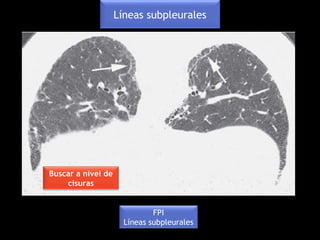

FPI

Líneas subpleurales

Buscar a nivel de

cisuras

Probable NINE

(esclerodermia)

Línea subpleural